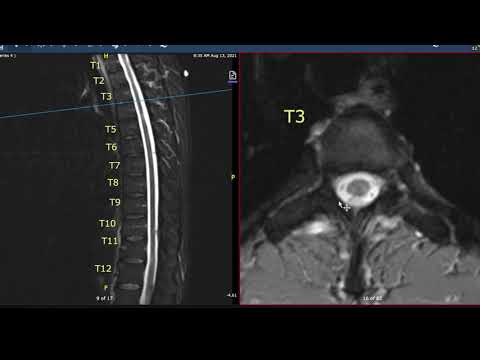

Multiple Sclerosis Vlog: Thoracic Spine MRI

Aaron Boster MDAug 30, 2021